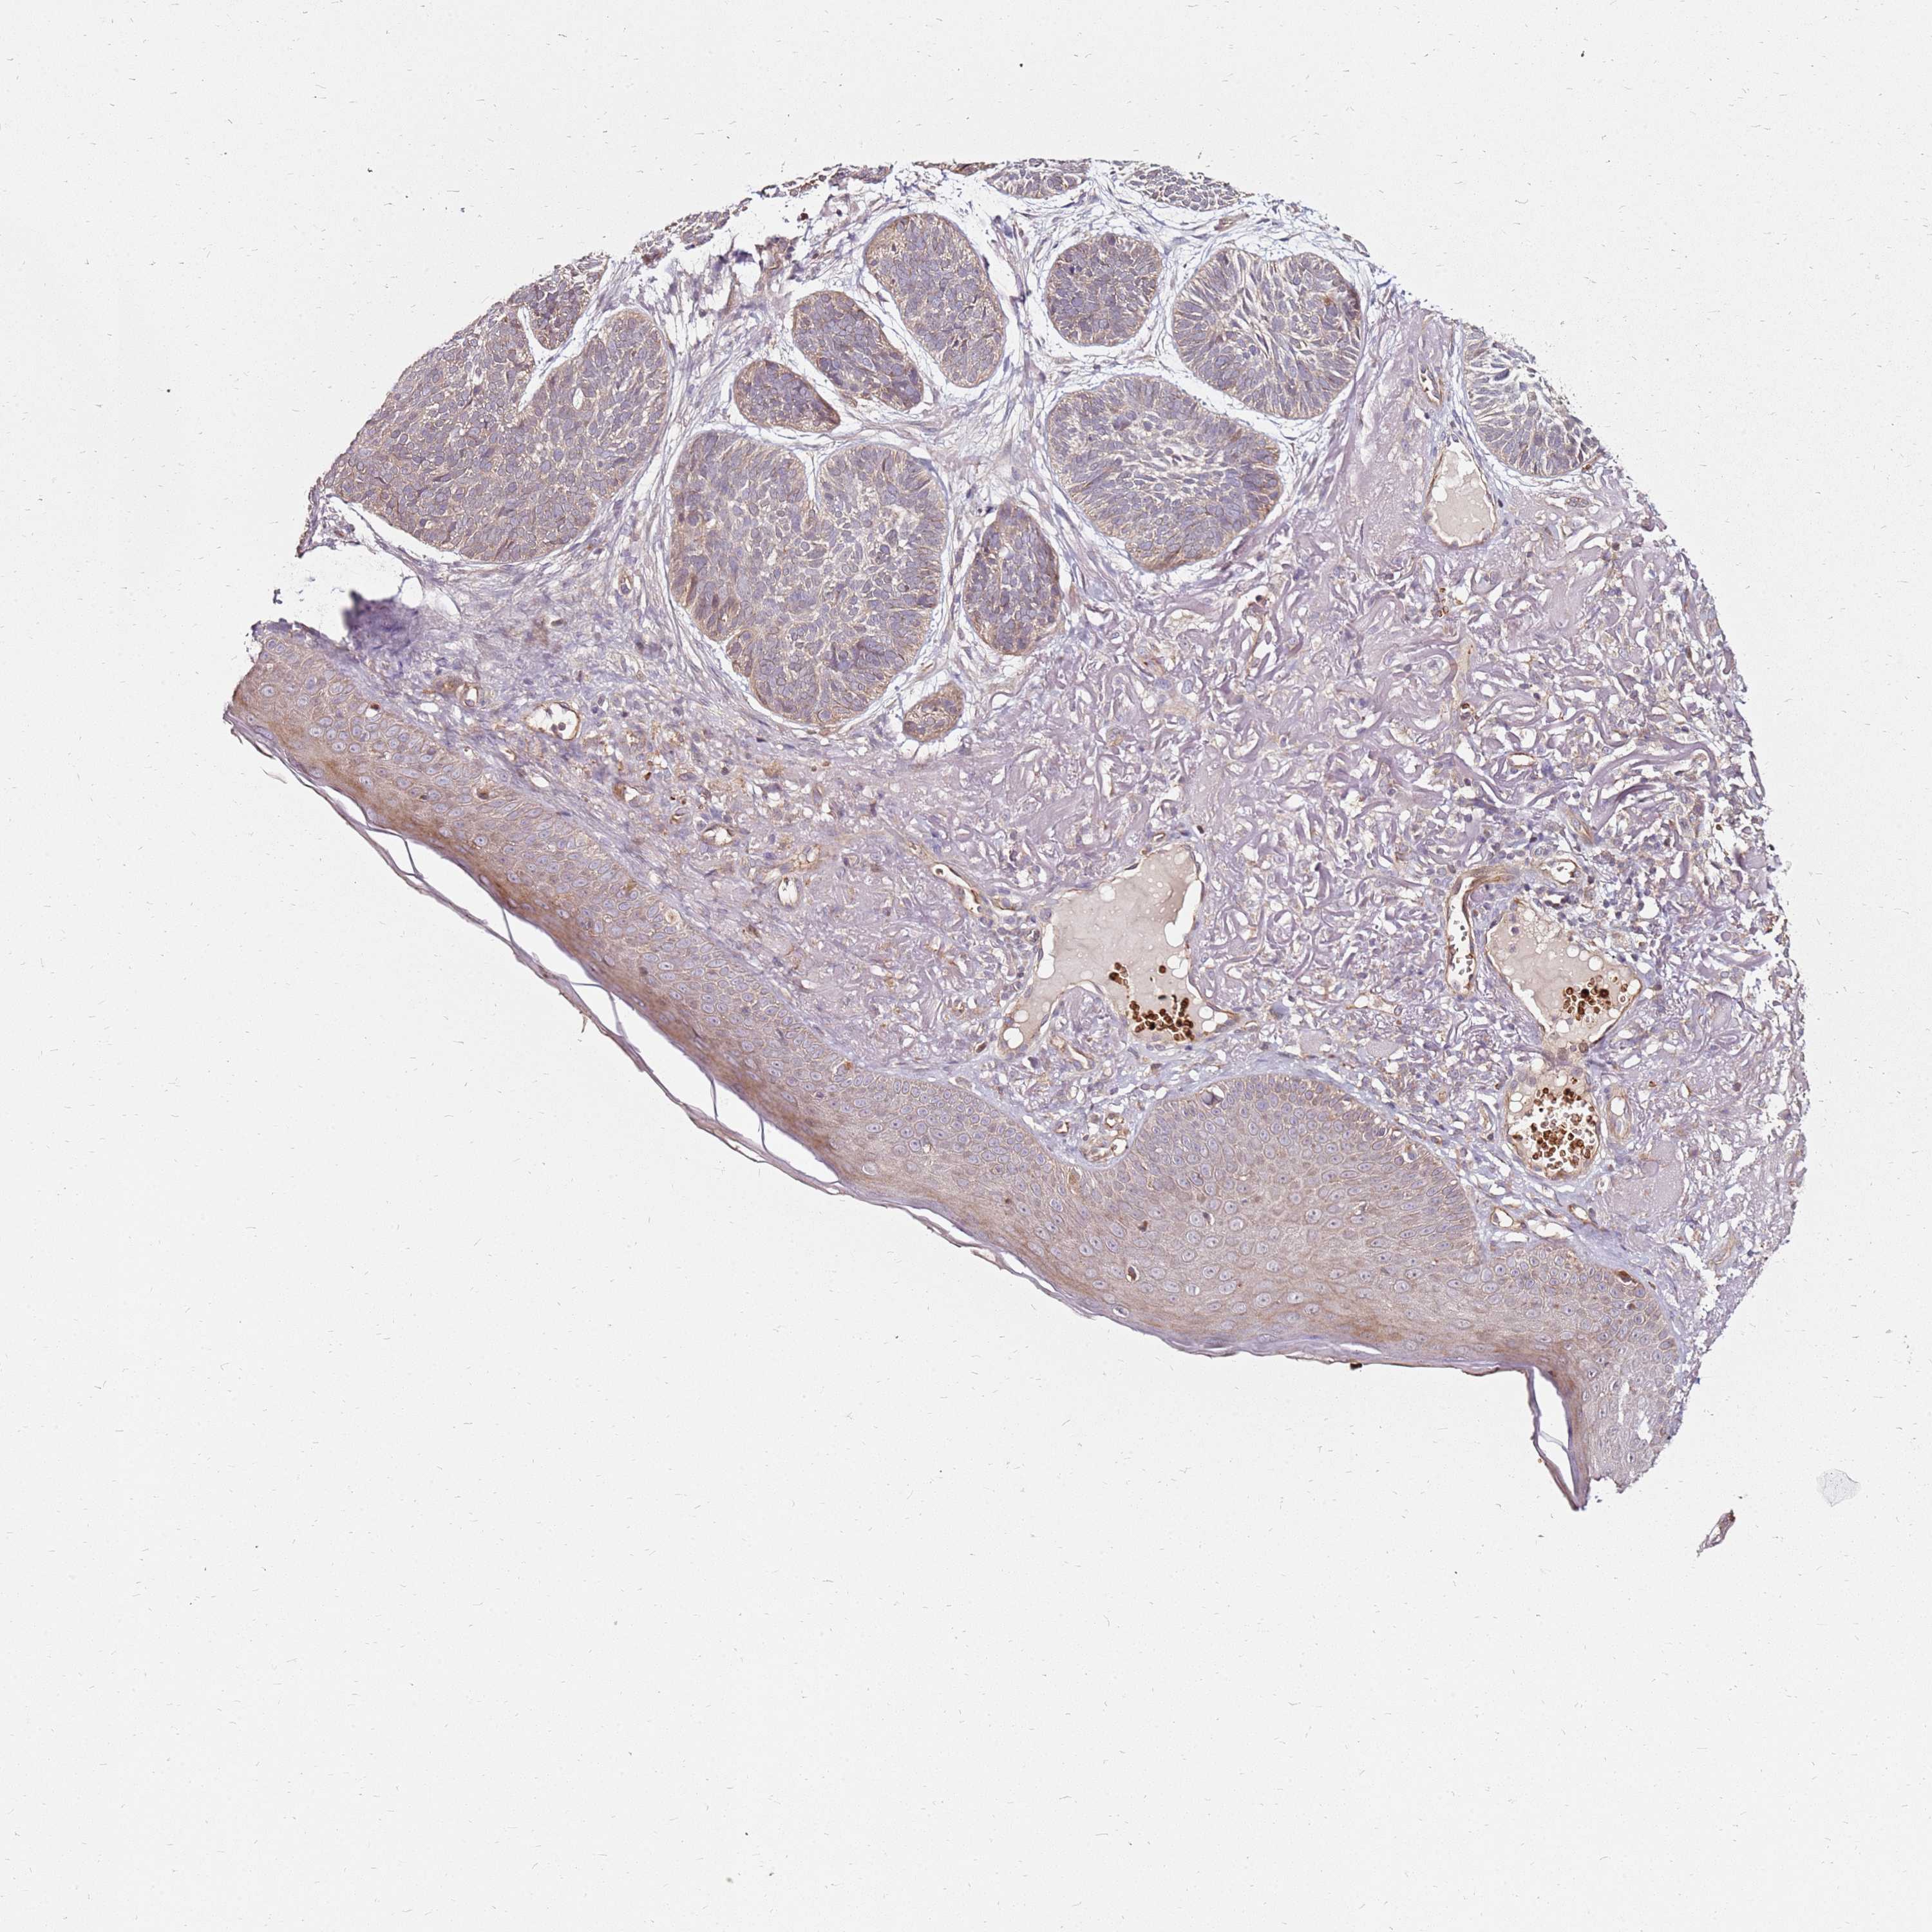

SKIN CANCER - Protein expressioni

A mouse-over function shows sample information and annotation data. Click on an image to view it in a full screen mode. Samples can be filtered based on level of antibody staining by selecting one or several of the following categories: high, medium, low and not detected. The assay and annotation is described here.

Each image is clickable and will lead to virtual microscopy that enables deeper exploration of all samples and also displays staining intensity scores, fraction scores and subcellular localization as well as patient and tissue information for each sample.

Antibody HPA045781

Squamous cell carcinoma, metastatic, NOS

Squamous cell carcinoma, NOS